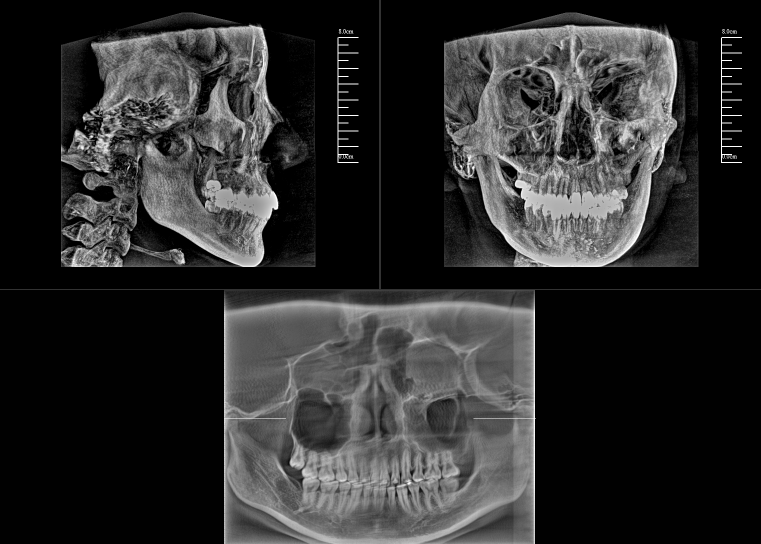

CBCT,全稱“錐束計算機斷層掃描(Cone-Beam Computed Tomography,CBCT)”,由球管和平板探測器組成。與全科CT的閉環圓孔設計不同,數字化口腔CBCT采用開放式結構以保持其靈活性。

對于口腔內科疾病,牙片和全景片已具有較高診斷效果;但對于牙體牙髓病,2D成像較容易發生影像重疊的情況,無法進一步明確根管和其他周圍組織的三維信息,容易出現漏診或誤診根裂的情況。這就需要三維斷層成像,即數字化口腔CBCT。

數字化口腔CBCT是從三維的角度,即矢狀位、冠狀位和橫斷位來顯示病變組織和正常組織結構,有效的避免了2D圖像固有的缺陷,如正常組織器官的影像重疊,投射角度變化所致的影像扭曲、變形等,大大提高了診斷能力。

數字化口腔CBCT能在十幾秒時間內完成患者口腔掃描,進而生成高精度的三維影像,徹底解決了牙片機、全景機等傳統口腔X射線設備影像重疊、畸變的問題。可以360°全方位立體觀測牙床的骨質密度、牙槽骨本身的高度、寬度等數據,不僅能重建整個顱面區的結構,對頜面骨質結構進行測量,而且還能重建精細的解剖細節。